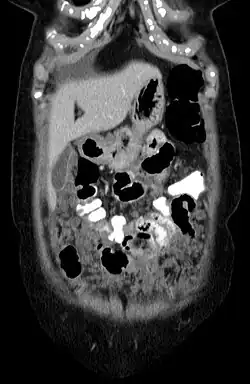

Das Mesotheliom ist ein diffus wachsender Tumor, der sich aus der dünnen Gewebeschicht entwickelt, die viele der inneren Organe bedeckt (Mesothel).[1][2] Am häufigsten ist die Auskleidung der Lunge und der Brustwand betroffen, seltener die Bauchdecke, der Herzbeutel oder der Hodensack. Zu den Anzeichen und Symptomen eines Mesothelioms gehören Kurzatmigkeit aufgrund von Flüssigkeit in der Lunge, ein geschwollener Bauch, Schmerzen in der Brustwand, Husten, Müdigkeit und Gewichtsverlust. Diese Symptome treten in der Regel langsam auf.

- im Peritoneum, 5–17 %

Mesotheliome sind oft schwer zu diagnostizierende, relativ seltene (ca. 3000 neue Fälle pro Jahr in den USA) Bindegewebstumore des Mesothels, vor allem der Pleura. Männer sind häufiger von der Erkrankung betroffen (Wahrscheinlichkeit ca. 1:1000 bzw. 4:1, je nach Quelle). Nach aktuellen Erkenntnissen wird das Mesotheliom zumeist durch Asbesteinwirkung (hier v. a. die langfasrigen Amphibole), Glasfaserstaub oder Toxikose durch Zigarettenrauch und andere exogene Schadstoffe hervorgerufen. Vereinzelt sind auch Fälle nach Strahlentherapie von Hodgkin-Lymphomen und anderen malignen Krebserkrankungen aufgetreten. Formen, die primär im Mesothel des Bauchfells oder Herzbeutels auftreten, sind wesentlich seltener. Das Pleuramesotheliom ist eine charakteristische Tumorform in Folge einer Asbestose und eine der ersten anerkannten Berufserkrankungen, da besonders Arbeiter in der asbestverarbeitenden Industrie und Bau- und Werftarbeiter betroffen sind, was auch die erhöhte Inzidenz bei Männern erklärt.